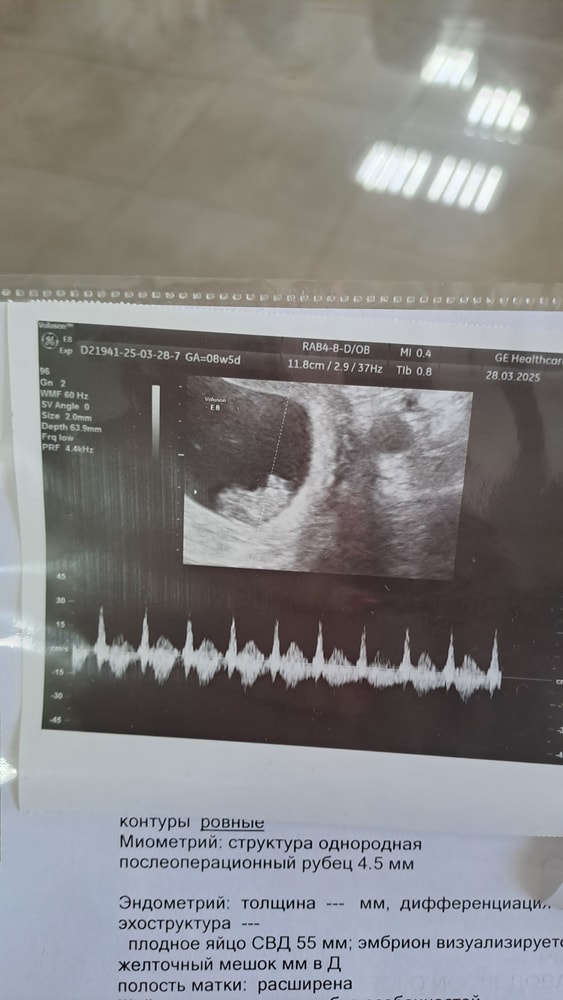

Узи 8 недель 5 дней ❤️

У нас все хорошо, малыш уже 21 мм, это Вам не хиханьки да хаханьки)